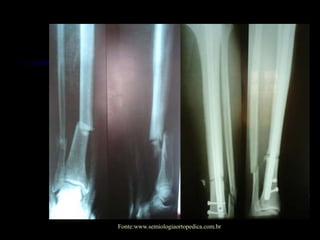

Fonte:www.semiologiaortopedica.com.br